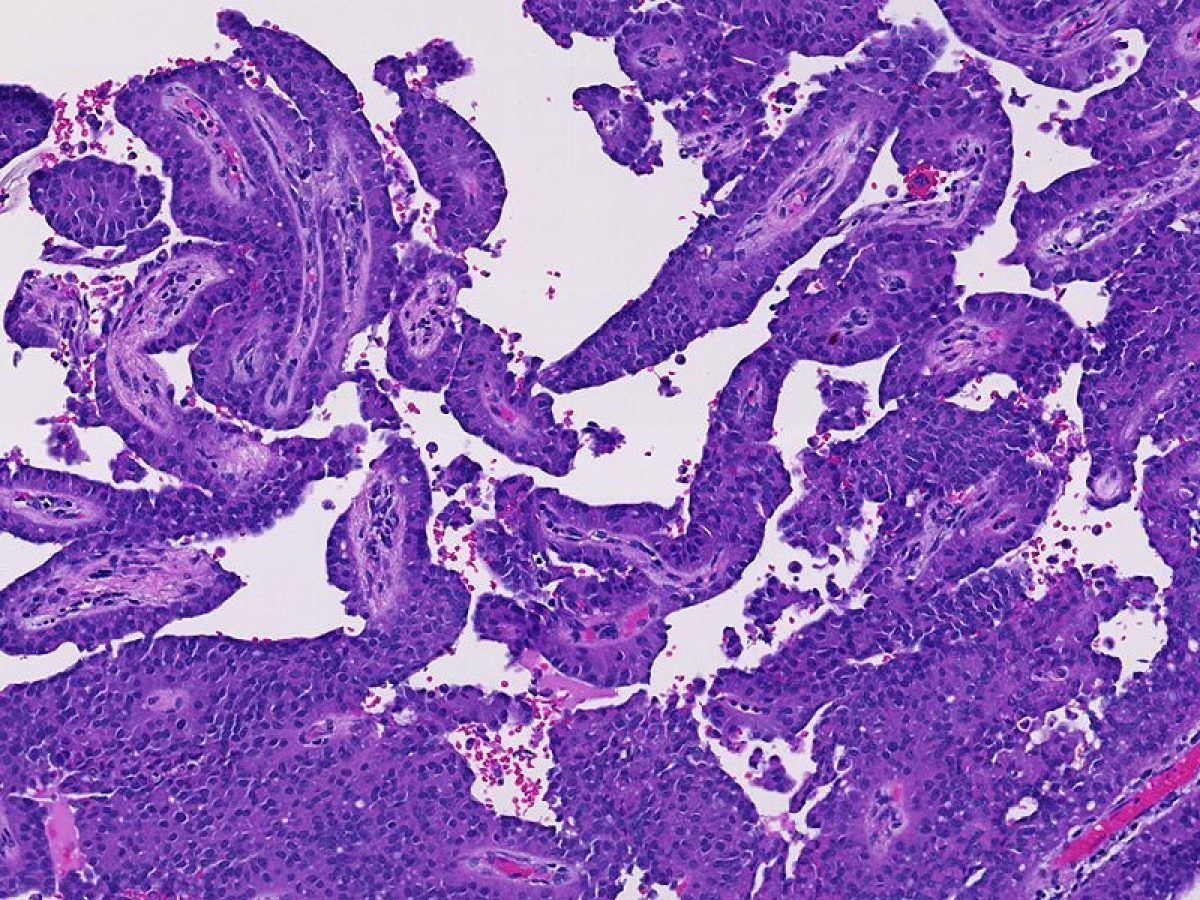

A term used to describe certain tumors which grow in finger-like projections. Pathologists use this term to describe some precancerous lesions in the pancreas (intraductal papillary mucinous neoplasm).

A term used to indicate that cancerous cells are present in the duct but have not yet invaded deeper tissues.

The form of cancer that most people are talking about when they refer to "cancer of the pancreas." These tumors account for 75% of all pancreas cancers.

Microscopically, adenocarcinomas form glands. These tumors can grow large enough to invade nerves which can cause back pain. They also frequently spread (metastasize) to the liver or lymph nodes. If this happens the tumor may be considered unresectable.